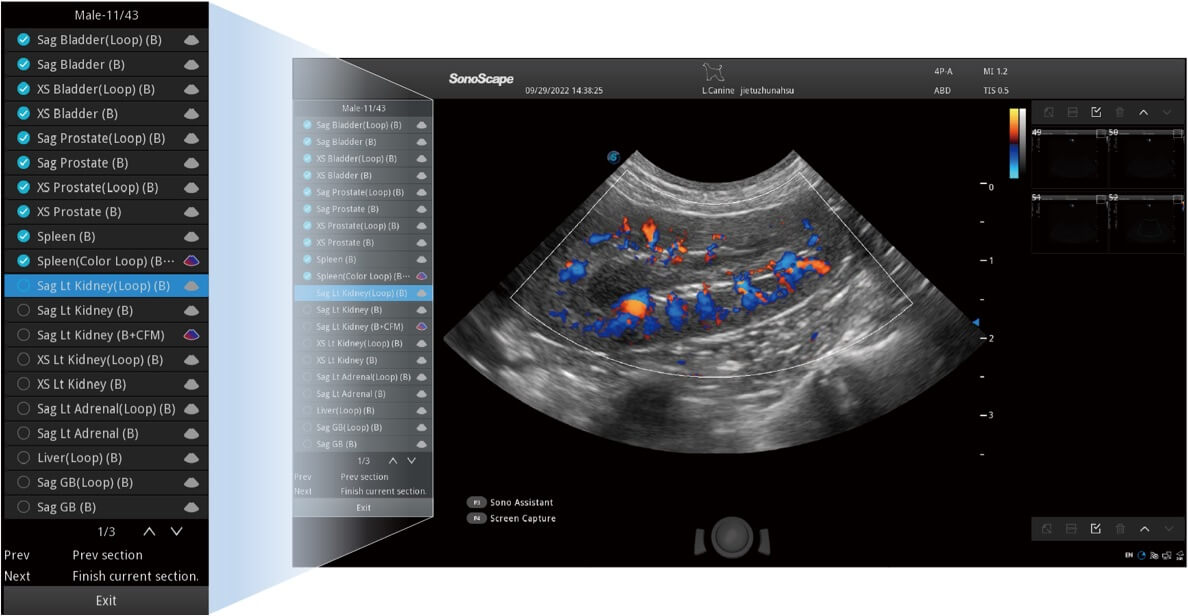

ProPet 60 作为一款高端台式动物超声设备,为动物医生的日常诊断提供了一系列贴合动物临床需求、解决临床实际问题的高级成像功能。凭借全系列高清探头,满足医生对腹部、心脏、生殖、浅表、肌骨等成像的所有需求,切实帮助您提升检查效率,提高诊断信心。

动物是人类最亲密的朋友和最值得信赖的伙伴。开立医疗也一直致力于探索动物专用的超声影像解决方案。 全新推出的ProPet系列,是开立在动物超声影像智能化、专业化、精准化的一次跨越式革新。动物不能用言语来表述自己的不适,通过超声影像,ProPet系列搭建了动物医生与不同物种沟通的“桥梁”,为动物医生注入了“治愈之力”。